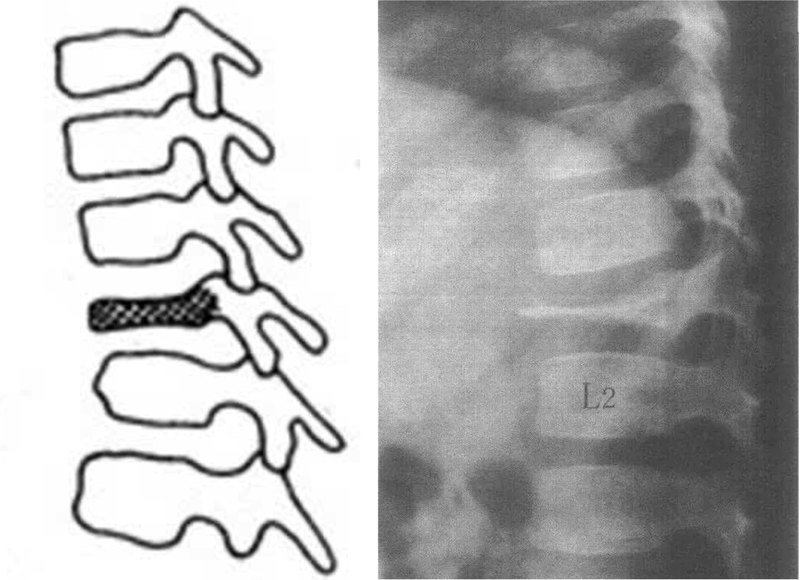

椎體由一個(gè)原發(fā)骨化中心和上下骺板的兩個(gè)次發(fā)骨化中心(環(huán)狀骨骺)發(fā)育形成。如椎體原發(fā)骨化中心發(fā)生骨軟骨病,稱為原發(fā)骨骺骨軟骨病,因病后椎體呈扁平狀,又稱扁平椎,該病由?Calve于?1924年首先報(bào)道,命名為?Calve?病。如果椎體骺板次發(fā)骨化中心發(fā)生骨軟骨病,則是我們前面已經(jīng)講過的次發(fā)骨骺骨軟骨?。ㄐ蓍T病)。扁平椎發(fā)生于兒童,主要侵犯椎體,癥狀不重,且可自行恢復(fù),但可有腰背痛及常遺留不同程度的畸形,可因腰背痛及腰背畸形而就診。扁平椎確鑿的病因尚不明確,①?一般認(rèn)為本病為椎骨血供障礙,引起原發(fā)骨化中心缺血壞死。導(dǎo)致血運(yùn)障礙的原因,有認(rèn)為是椎骨終末動(dòng)脈發(fā)生非感染性或機(jī)械性血管栓塞;也有認(rèn)為椎骨不存在終末動(dòng)脈,無吻合的骨血管是不存在的,難以證明血管栓塞發(fā)生于椎體的中心部位,即使有一支血管栓塞,也不會(huì)引起整個(gè)椎體中心壞死;還有提出血管狹窄,如糖尿病、動(dòng)脈硬化、大劑量激素和放射治療等可以引起,然而兒童此類疾病很少,顯然不是主要原因。②?外傷學(xué)說:發(fā)病部位多為負(fù)重大、活動(dòng)多的節(jié)段,如胸腰段或腰段,因而外傷導(dǎo)致本病是可能的。兒童過度負(fù)重、引起脊椎及周圍軟組織的血管損傷,使椎體的血供障礙而導(dǎo)致缺血壞死,其中積累性損傷特別受到重視。③?近年來對(duì)病椎的活檢提示病變可能是嗜伊紅細(xì)胞肉芽腫所致。扁平椎的病理過程分為缺血壞死、修復(fù)再生和痊愈三期。骨壞死引起周圍結(jié)締組織生長活躍,包繞壞死區(qū)并伸入其中,使骨骺發(fā)生碎裂,受重力擠壓而變扁平。以后壞死骨逐漸被吸收、消失,長入骨骺內(nèi)的結(jié)締組織和軟骨分化成骨,椎體的骨結(jié)構(gòu)又逐漸重建。在椎體內(nèi)一處病變可有壞死、新生和修復(fù)三種時(shí)相同時(shí)存在,且可反復(fù)發(fā)生,交替進(jìn)行。扁平椎多見于2~10歲的兒童,男女發(fā)病率相近。好發(fā)于胸椎中段,其次為腰椎。多為單發(fā),偶有累及幾個(gè)椎體。該病起病隱匿,多數(shù)患兒無明顯癥狀而被忽略,部分主訴有輕至中度的背痛、乏力,可有肌肉痙攣、夜啼。病變椎體處有深壓痛或叩擊痛,檢查可發(fā)現(xiàn)脊柱活動(dòng)受限,病變晚期可出現(xiàn)脊柱后凸畸形。發(fā)病2個(gè)多月后,病情逐漸趨于穩(wěn)定,但畸形不會(huì)立即消失。X線檢查早期只見椎間隙狹窄,數(shù)月后可見椎體邊緣不規(guī)則,逐漸密度增高,椎體變扁增大,呈后凸畸形。變扁的椎體可為上下面凹陷畸形或完全變扁平,呈硬幣樣。晚期修復(fù)后的椎體可逐漸增高,并較上下椎體增寬,椎弓根及附件不受侵犯,無椎旁膿腫或軟組織腫塊陰影,病變愈合后椎體的高度及密度可完全或部分恢復(fù)。鑒別診斷方面:第一,椎體嗜伊紅細(xì)胞肉芽腫,引起椎體慢性萎縮,晚期椎體壓縮變扁平,或有認(rèn)為此病即是扁平椎。第二,椎體中心型結(jié)核,常有結(jié)核中毒癥狀,X線片可發(fā)現(xiàn)相鄰椎體病變,或有跳躍性病變,壓扁的椎體密度不增加,椎間隙變窄,椎旁可有膿腫影?;純簯?yīng)適當(dāng)臥床休息,減輕受累椎體壓力,有利于椎體恢復(fù)生長。病情穩(wěn)定后鍛煉腰背肌,以預(yù)防背痛。其他物理療法如超短波、微波、礦泉浴、按摩等,可緩解肌肉痙攣。同時(shí)口服維生素?A、D、鈣劑等。針對(duì)后凸畸形,早期可用?Milwaukee?支具、矯形背心和矯形鍛煉;少數(shù)后凸嚴(yán)重而病情穩(wěn)定者,可行截骨矯形植骨融合內(nèi)固定術(shù)。